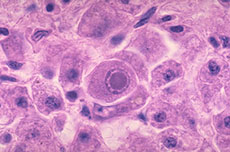

子宫颈鳞状上皮内病变(SIL)

疾病介绍:是与子宫颈浸润癌密切相关的一组子宫颈病变,常发生于25-35岁如女。大部分低级别鳞状上皮内病变LSIL)可自然消退,但高级别鳞状上皮内病变(HSIL)具有癌…【详细】